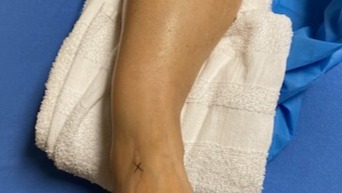

As some of you may have heard, my amazing wife Jennifer broke both the bones in her right leg on March 3rd. Luckily, it wasn't a compound fracture but pretty close to being so. She had an amazing team of surgeons put her back together and now she is on the long road to a healthy recovery. Racquetball is on hold and she is never roller skating again. As we deal with the mountain of medical costs we have dug into our reserves during her work hiatus. Jen is a free-lance, self-employed contractor working on various TV productions in the DFW Metroplex. Since the accident, Jen had to cancel several jobs that she was booked for. Like a lot of us, we are a dual income household so this income loss hurts a bit.